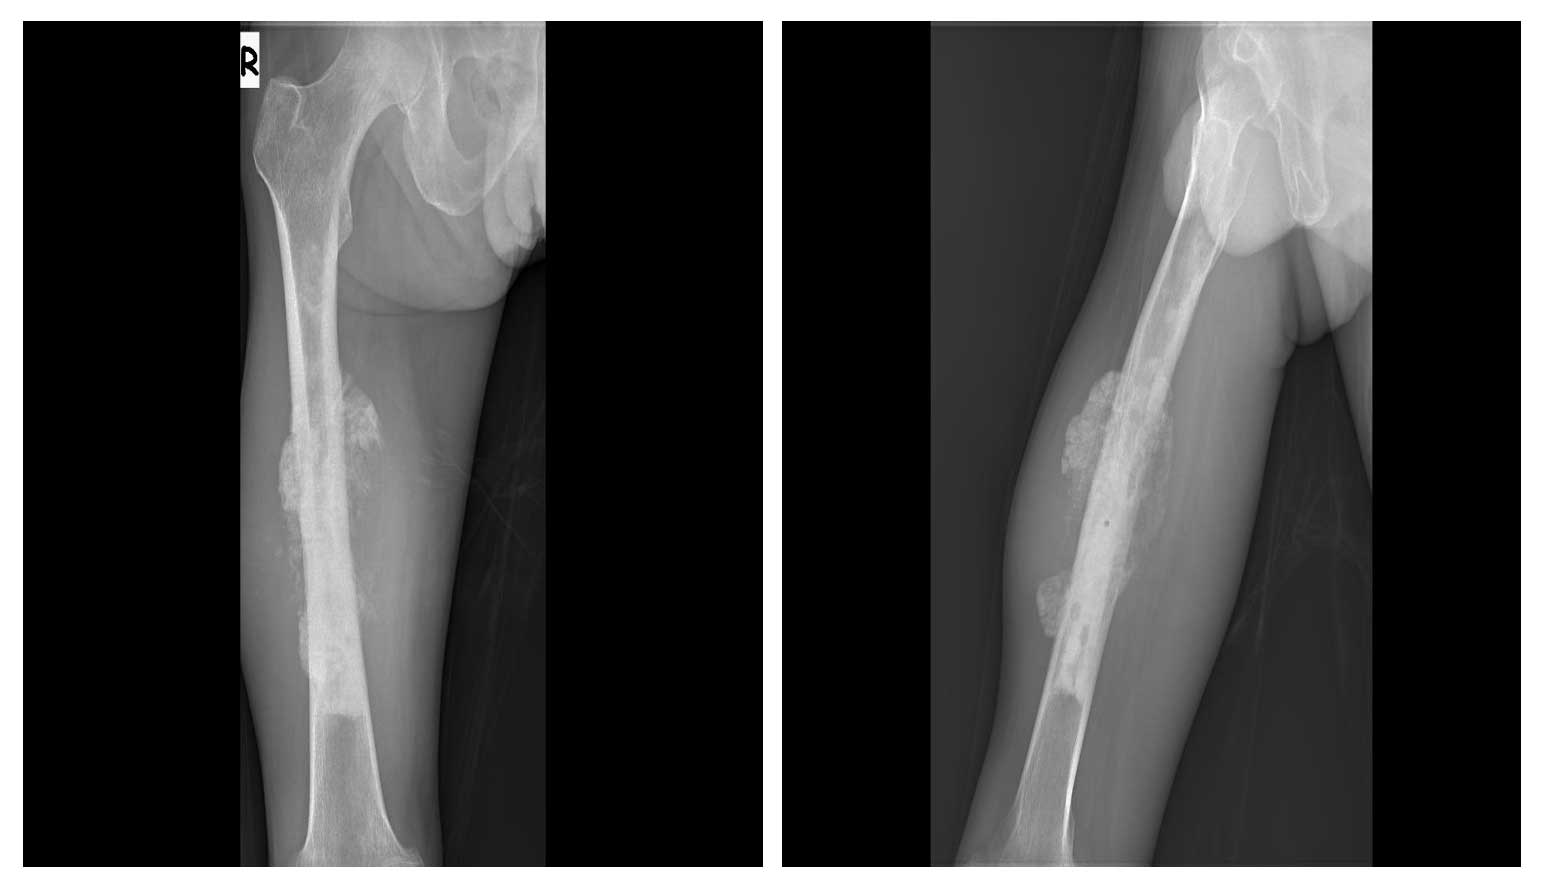

Ameliyat Öncesi: Röntgende femur diafizde düzensiz sınırlı periost reaksiyonuna neden olan sklerotik tümör dokusu görülmekte.